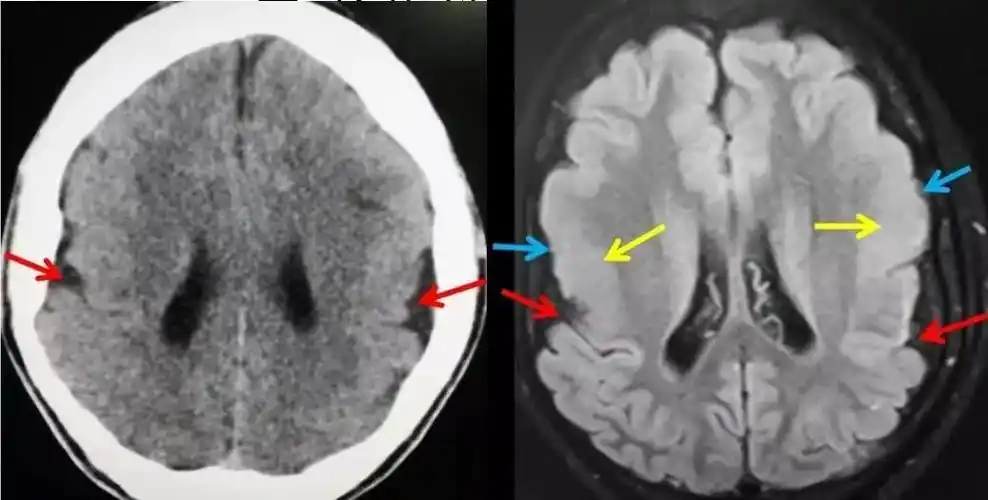

巨脑回畸形西安高尚医学影像病例

高尚病例:巨脑回畸形

巨脑回1

行过程中受阻,导致脑组织不同程度的发育畸形,包括无脑回-巨脑回畸形